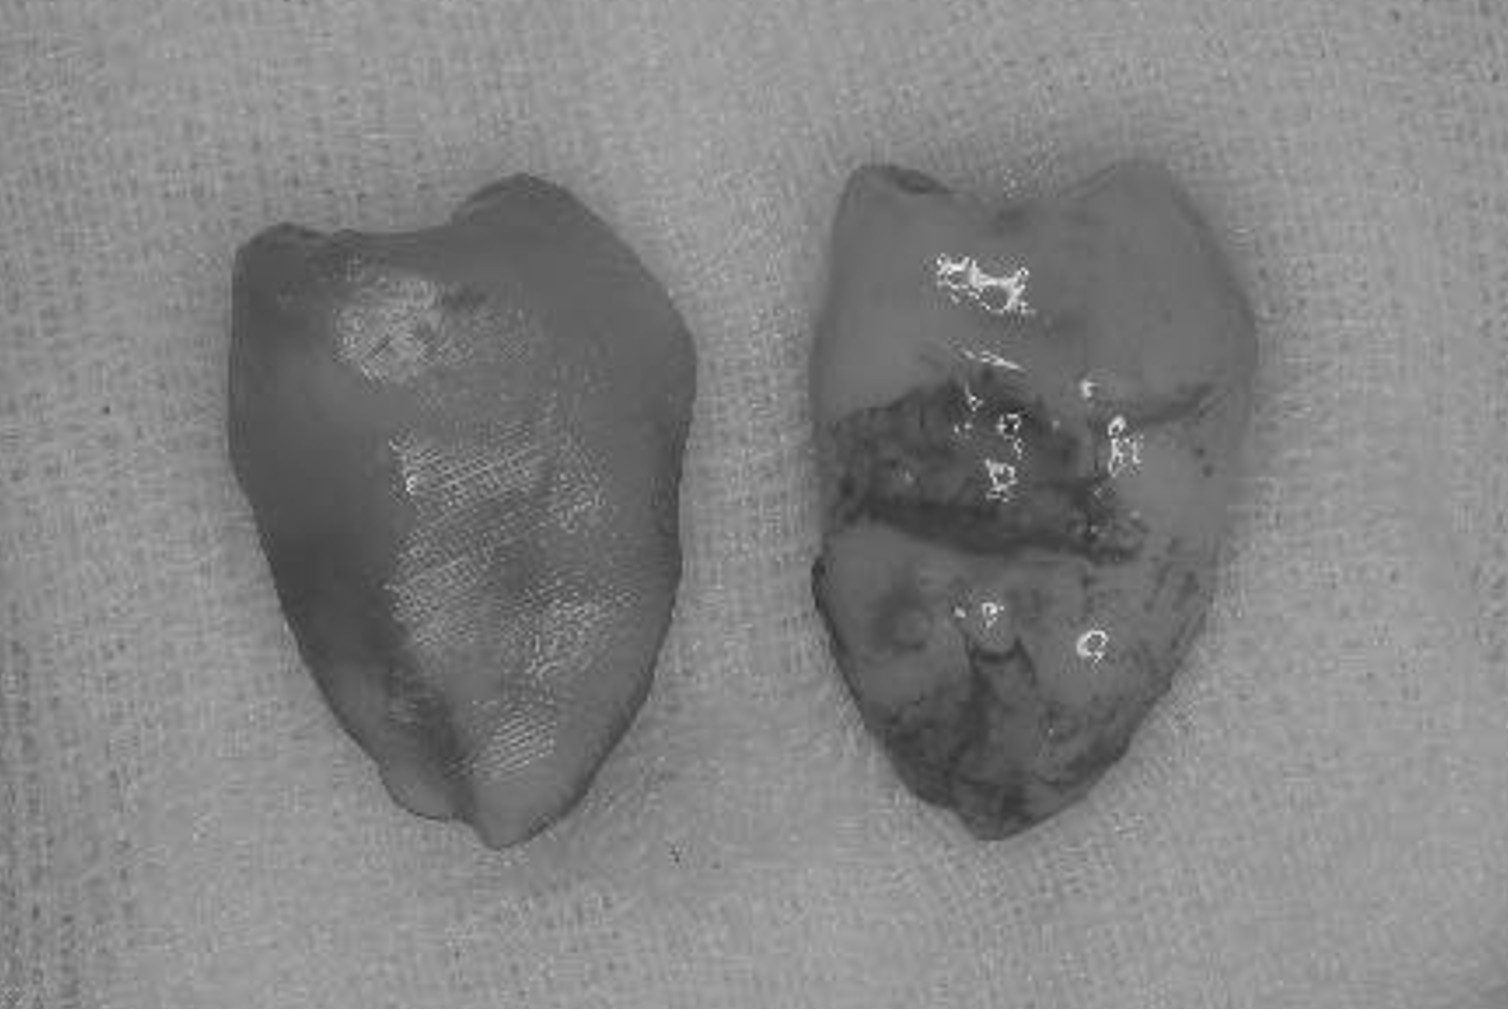

症例3

治療の流れ

親知らずの抜歯

抜歯が必要になった際に余っている親知らずがあれば移植歯として利用することができます。 術前に撮影したCT画像から3Dプリンターを用いて親知らずのレプリカを作製することで、親知らずが乾燥することを防ぎ、成功率が上がるよう努力しています。 |